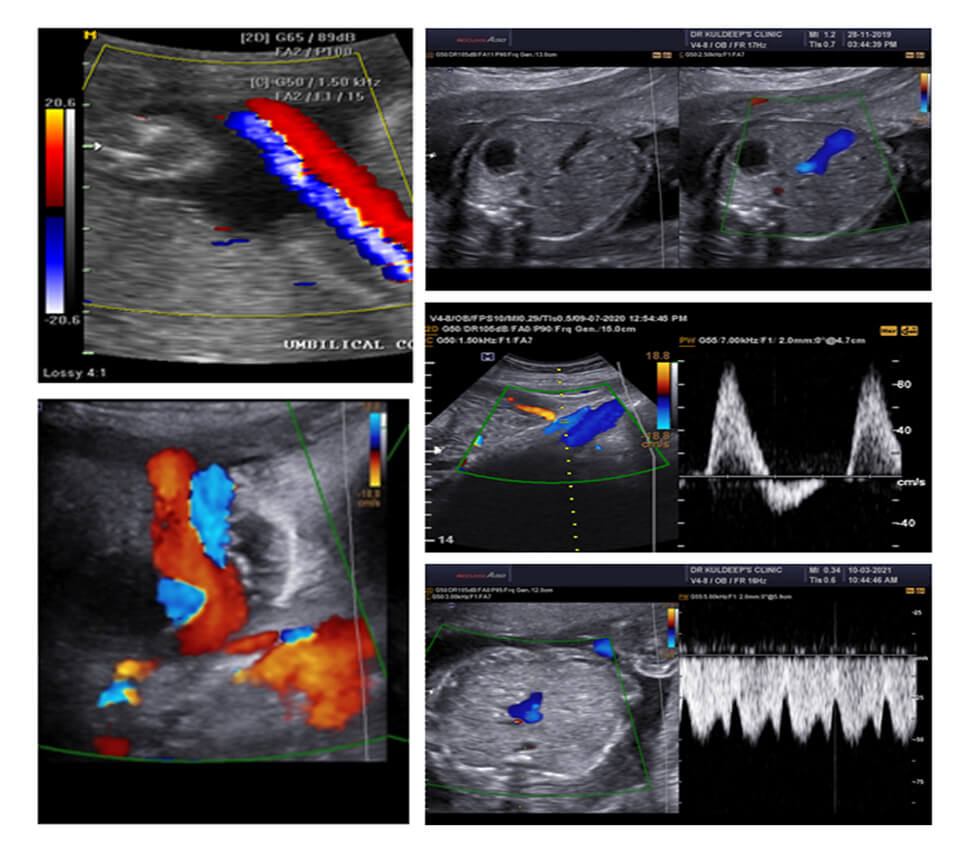

COLOR DOPPLER OBSTETRICS

Session 1 COLOR DOPPLER BASICS

KNOW YOUR MACHINE

Session 2 SHOW YOUR MACHINE

Session 3 DV/TR/UTERINE ARTERIES AT 11-14 WEEKS

Session 4 DV/UTERINE ARTERIES IN SECOND TRIMESTER + ASSIGNMENT SUBMISSION

Session 5 FETAL BIOMETRY APPROACH WITH MEASUREMENTS AND GRAPHS

Session 6 UMBILICAL/MCA/DV/AORTIC ISTHMUS + ASSIGNMENT SUBMISSION

Session 7 UMBILICAL/MCA/DV/AORTIC ISTHMUS + ASSIGNMENT SUBMISSION

Session 8 REVISION: START TO FINISH

CDC : PREGNENCY (24-40)

24-40 WEEKS

UMBILICAL

UTERINE ARTERIES

DV

MCA PI AND PSV

CPR

AORTIC ISTHMUS

DESCENDING AORTA